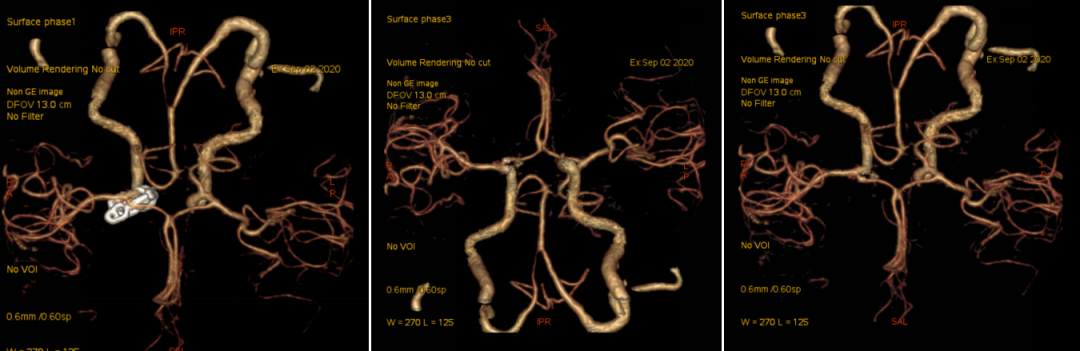

入院后予完善头颅DSA检查提示左侧颈内动脉眼动脉段动脉瘤;头颅MR提示脑内多发陈旧梗死,告知其介入栓塞、开颅夹闭等治疗方式、利弊、风险及费用等,患方商量后决定行开颅动脉瘤夹闭术。

头颈部CTA

术前DSA

入院后予完善MRI及头颅DSA检查提示右侧颈内动脉眼动脉段动脉瘤;告知其介入栓塞、开颅夹闭等治疗方式、利弊、风险及费用等,患方商量后决定行开颅动脉瘤夹闭术。

科内讨论后认为:患者颈内动脉床突旁大动脉瘤诊断明确,患者动脉瘤破裂出血,需急诊手术治疗。术中应先在颈部暴露颈内动脉。采用Dolenc入路硬膜外磨除前床突及视神经管。术中注意保护好眼动脉。暴露动脉瘤后可孤立动脉瘤,并在颈部穿刺颈动脉并逆向抽吸,降低动脉瘤的张力后塑形夹闭动脉瘤。